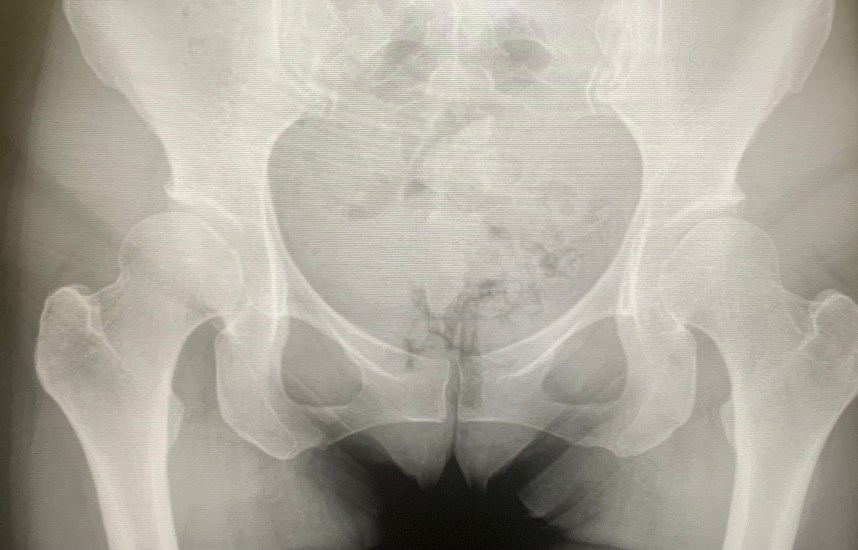

Untreated chronic bilateral hip dysplasia Image Hip Dysplasia X Ray Measurements Radiographic assessment of acetabular dysplasia or adult hip dysplasia includes plain radiographs of the pelvis and additional planes as the false profile view of. Adult dysplasia of the hip is a disorder of abnormal development of the hip joint resulting in a shallow acetabulum with lack of anterior and lateral coverage. The findings in females along with the clinical history. Hip Dysplasia X Ray Measurements.